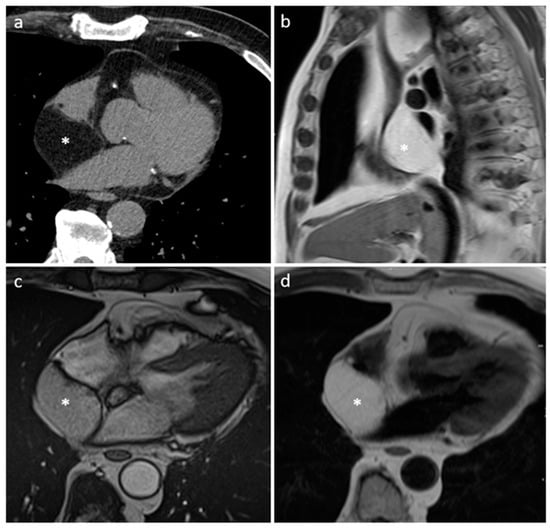

3.10. Hematoma

| Hematoma | Usually adulthood, previous surgery, traumatic heart injury, coagulopaty, anticoagulants | Pericardium | Usually, asymptomatic | Previous cardiac surgery, mass near surgical site or clips, usually well-defined borders. Usually absent contrast-enhancement | Acute phase: echo-lucent Chronic phase: mass like and echogenic | Heterogeneous, clips, hyperdense in acute phase, density decrease in chronic phase, calcific components in chronic hematoma | Acute: hyper T1w and T2w Subacute: heterogeneous with hyper T1 and T2w areas Chronic: hypo T1w and T2w with dark peripheral rim. No internal enhancement, possible rim enhancement |